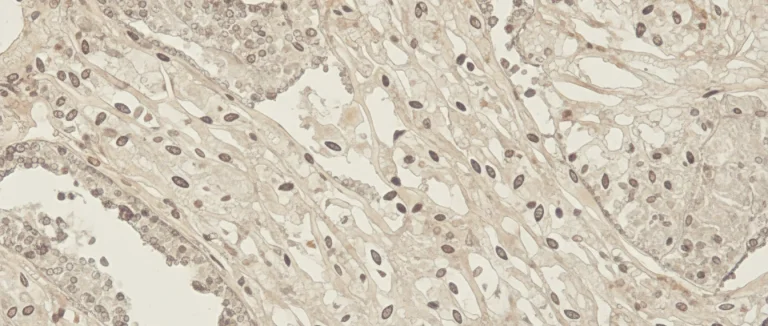

Наиболее распространённый способ – денситометрия двойной энергетической рентгеновской абсорбциометрии (DXA). Этот тест измеряет минеральную плотность костей (BMD) в граммах на квадратный сантиметр и позволяет классифицировать состояние кости как нормальное, остеопения или остеопороз.

Для более детального анализа структуры кости могут использоваться компьютерная томография (CT) и магнитно-резонансная томография (MRI). Эти методы позволяют оценить микроструктуру и выявить скрытые микротрещины, которые не видны на обычных рентгеновских снимках.